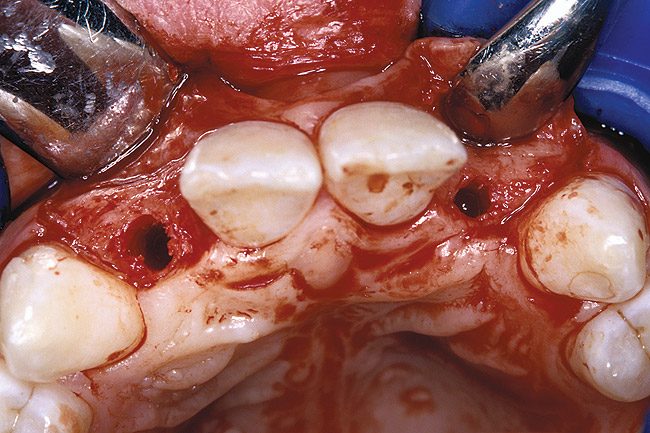

Periapical radiographs were taken to help determine the mesial-distal inclinations of the adjacent tooth roots (Figure 1). The radiographs revealed a serious issue, convergent roots for the right canine and right central, which eliminated that area as a potential implant-receptor site. The space between the left central and canine teeth was minimal, although the roots were relatively parallel. Clinical examination (manual palpation of the root eminences superiorly to the vestibule on the right side) confirmed the root convergence (Figure 2). The flat, wide zone of the keratinized tissue and lack of interdental papilla was evident for the missing right lateral incisor. There was a marked difference in clinical appearance for the left lateral, which could impact the eventual plan of treatment (Figure 3). Other significant clinical findings included bilateral facial bone concavities, which existed as a result of the congenitally missing tooth roots. As a diagnostic cue to the underlying bone topography, it is important to follow the demarcation between attached and unattached gingival tissue, and note the crestal width of the available keratinized tissue (Figure 4).

Before the day of surgery, the patient was seen by the orthodontist for the removal of the orthodontic brackets. The patient still was not pleased with the position of the two centrals, and it was determined that this would be addressed after implant placement (Figure 26). The anatomical variations of the crestal tissue and lack of interdental papilla can be appreciated in the close-up views of the right and left sites (Figure 27 and Figure 28). There were no surprises on the day of surgery as all of the decisions were made during the planning phase, before the scalpel ever touched the patient. The occlusal view of the CT 3D model revealed the wider alveolar ridge on the right side and thinner crest on the left side (Figure 29). This was confirmed when the full-thickness mucoperiosteal flaps were elevated, and the underlying bone revealed (Figure 30). The tooth-borne templates were designed to facilitate the drills and drilling sequence specific to the diameters of the predetermined implants (Figure 31). Each template contained an embedded 5-mm long stainless steel tube, which was approximately 0.2-mm wider than each drill (just wide enough to allow for the drills to rotate freely). Once positioned over the natural teeth, the template was secure and offered precision accuracy in transferring the implant locations from the original software-designed plan, allowing the potential for internal and external irrigation (Figure 32).

Figure 30  VIRTUAL PLANNING AND SURGERY The information gained from the 3D model was confirmed when the flaps were elevated.

Figure 30